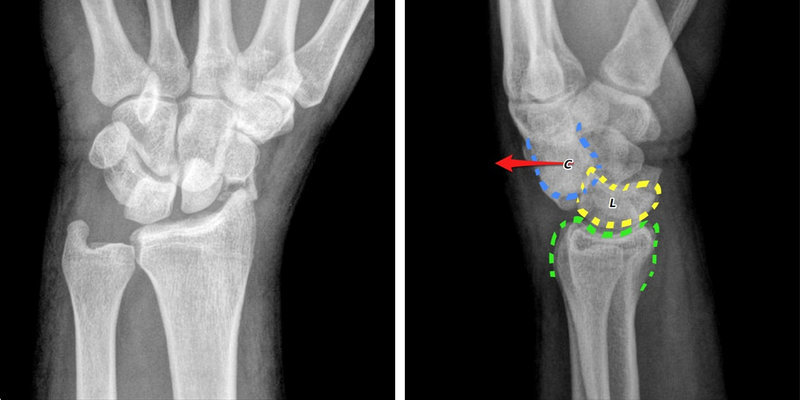

Để biết chính xác tình trạng cổ tay có vấn đề gì, bác sĩ sẽ chỉ định bạn chụp X-quang, CT hoặc MRI.